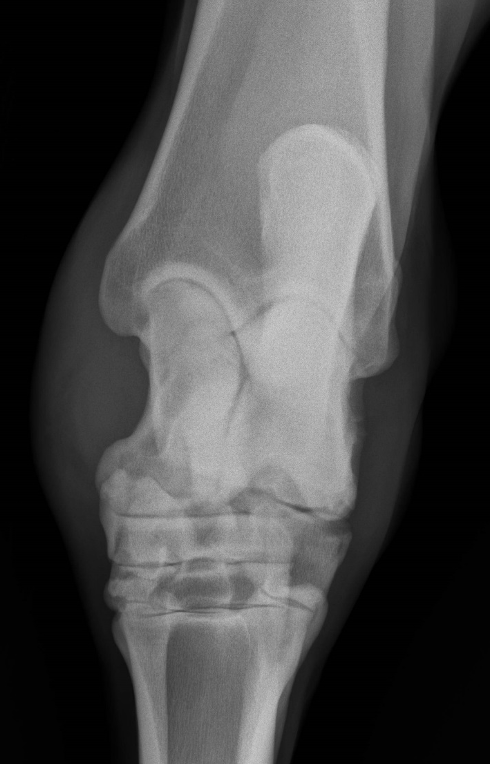

What is shown in this image?

consequences of tarsal bone collapse:

-narrow joint spaces

-abnormal shape of tarsal bones